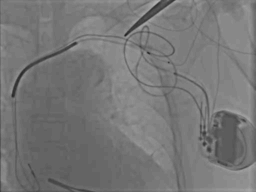

病例六

● 男,43岁,扩张性心肌病

● 术中见靶静脉狭窄,电极送入困难,采用球囊扩张、鞘中鞘技术送入电极